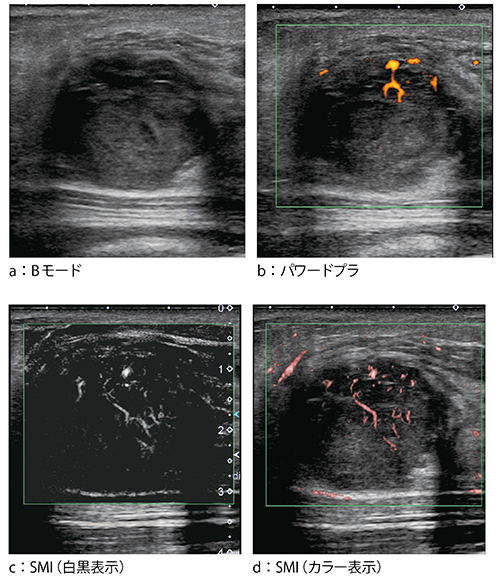

●症例5:乳管内乳頭腫(68歳)

症例5は,マンモグラフィ検診で右乳房に腫瘤を指摘された。Bモードでも囊胞内腫瘍が認められ(図7 a),68歳という年齢からがんを強く疑った。腫瘍は6〜7mmと小さく,パワードプラではほとんど血流を認めなかったが(図7 b),SMIでは腫瘍内部に入り込む血流が2,3本認められ,血流が多いと考えられた(図7 c)。しかし,エラストグラフィでは組織が非常に軟らかく(図7 d),診断に迷う所見であった。最終的にはVABを施行し,本症例は乳管内乳頭腫と診断された。

図7 症例5:乳管内乳頭腫(68歳)